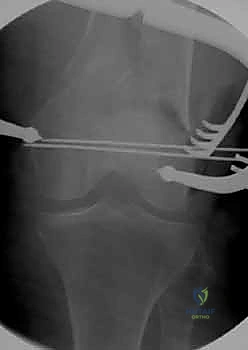

قبل بدء الجراحة، يتم رسم خطة دقيقة. يتم وضع المريض على طاولة العمليات المجهزة بأشعة (C-Arm) لضمان التصوير الفوري أثناء الجراحة.

المرحلة الثالثة: إرجاع العظم (Reduction)

هذه هي الخطوة الأكثر أهمية. يقوم الدكتور هطيف بإعادة القطع العظمية المكسورة إلى مكانها التشريحي الأصلي. إذا كان الكسر ممتداً داخل المفصل، يتم تثبيت السطح المفصلي أولاً باستخدام مسامير دقيقة لضمان سطح أملس يمنع الاحتكاك والخشونة مستقبلاً.

بعد التأكد التام من استقرار الكسر وحركة المفصل عن طريق الأشعة داخل غرفة العمليات، يتم إغلاق الجرح بطبقات متعددة باستخدام خيوط تجميلية لتقليل الندبات، ووضع أنبوب تصريف (Drain) لمنع تجمع الدم.